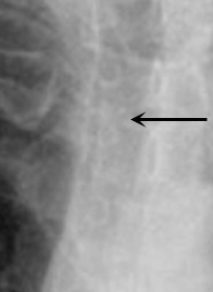

How is the trachea recognized?

The trachea is easily recognized because of tracheal rings and the lumen is filled with air.